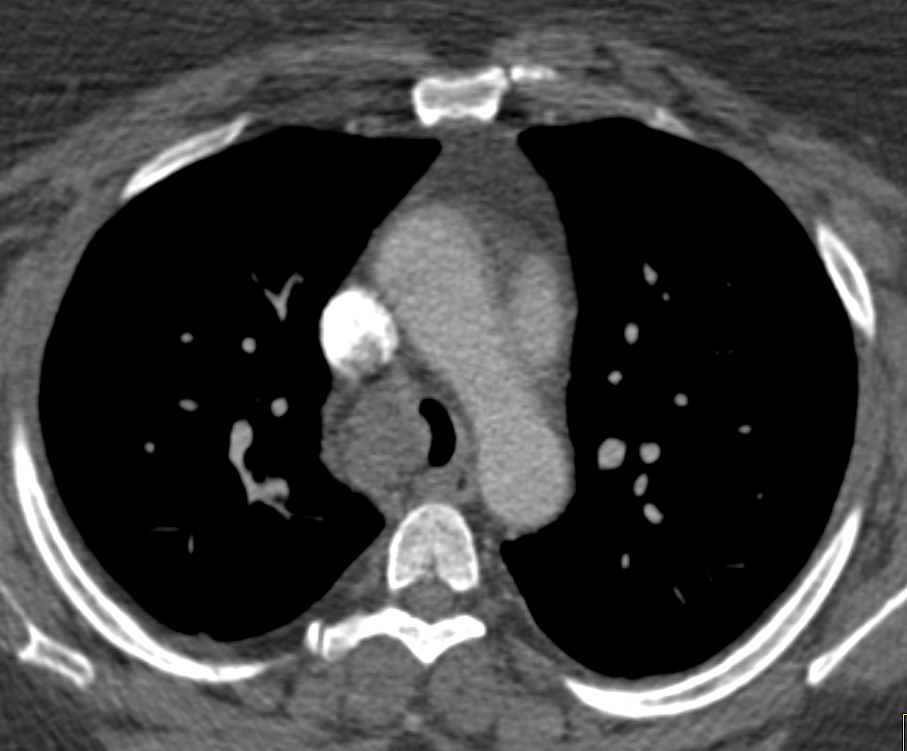

5) In this patient with cough the most likely dx is?

amyloidosis

metastatic tumor to trachea

adenoid cystic carcinoma

duplication cyst